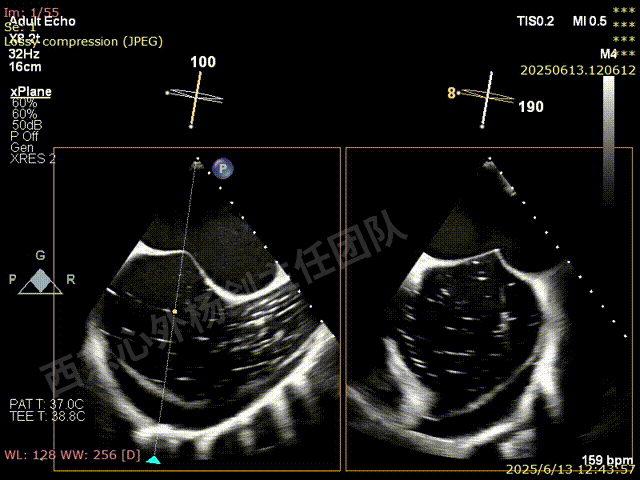

TAVR术后,全心增大,二尖瓣反流重度,三尖瓣反流重度。中量心包积液。左室严重增大,标准图像调整困难。主动脉瓣位带支架人工瓣膜瓣叶启闭正常,主动脉瓣位人工瓣上血流速度Vmax 148cm/s,PGmax 9mmHg,Vmean 86cm/s,PGmean 2mmHg, VTI 34.7cm,瓣周反流(轻)。估测肺动脉收缩压约49mmHg;左室收缩功能明显减低。LVEF:23%,EDV:364ml,ESV:221ml。

彩色血流示:二尖瓣反流缩流颈彩宽6.6mm,面积17cm²,容积30ml;二尖瓣瓣口面积6.6cm²,瓣环内径:左右径34mm,前后径34mm。2区瓣叶长度:前叶36mm,后叶20mm,叶环比1.6. 三尖反流面积17.2cm²,容积33ml,Vmax 291cm/s,PGmax 34mmHg。

TEER术前超声评估

二尖瓣后叶栓系严重,前叶相对错位,反流束沿2区分布广泛,2偏3区处存在反流。

反流宽度至少23mm,因影像调整困难,考虑实际反流更宽。